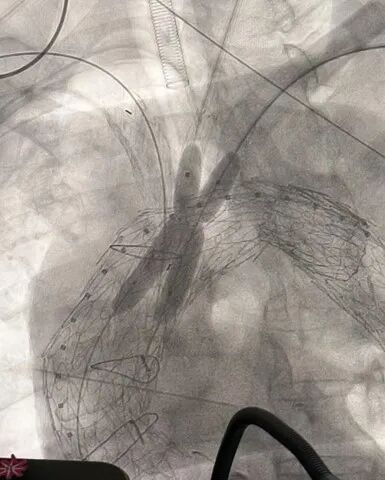

主动脉弓造影

2. 右侧肱动脉置入12Fr鞘至升主动脉,置入Mustang 10mm*80mm球囊,左右颈总动脉置入8Fr鞘。沿加硬导丝置入远端覆膜支架TGU343420定位后释放,继续置入近端覆膜支架TGU404020定位于冠脉吻合口上方释放。